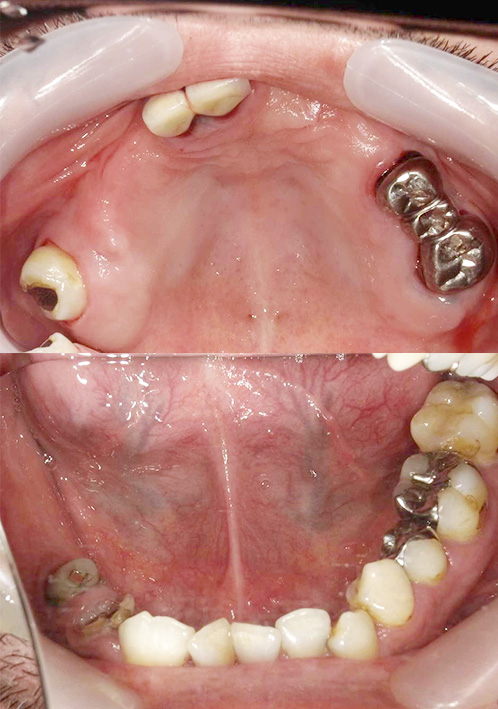

- 短期集中治療による治療例⑤

-

治療本数:27本

治療期間:1年

歯周外科治療併用・インプラント12本埋入■治療前 正面

↓ ■治療前 かみ合わせ

↓ ■治療後 正面

■治療後 かみ合わせ